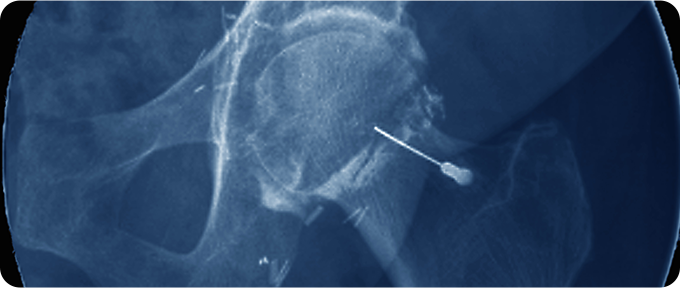

재생주사치료 치료 사진

재생주사치료

대퇴골두 무혈성 괴사의 재생주사치료는 손상된 조직의 재생을 촉진하고 혈류를 개선하기 위해 시행됩니다. 자가세포 치료(줄기세포 치료) 또는 성장인자 주사(PRP)를 사용하여 손상 부위의 회복을 돕습니다. 이는 초기 또는 중등도의 병변에서 효과적일 수 있으며, 수술 대신 사용할 수 있는 옵션으로 고려됩니다.